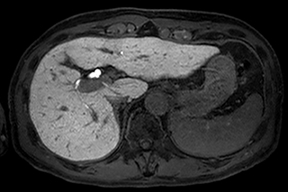

内臓動脈瘤への経皮的塞栓術

脾門部の動脈瘤に対して塞栓用コイルにて塞栓術を施行しています。